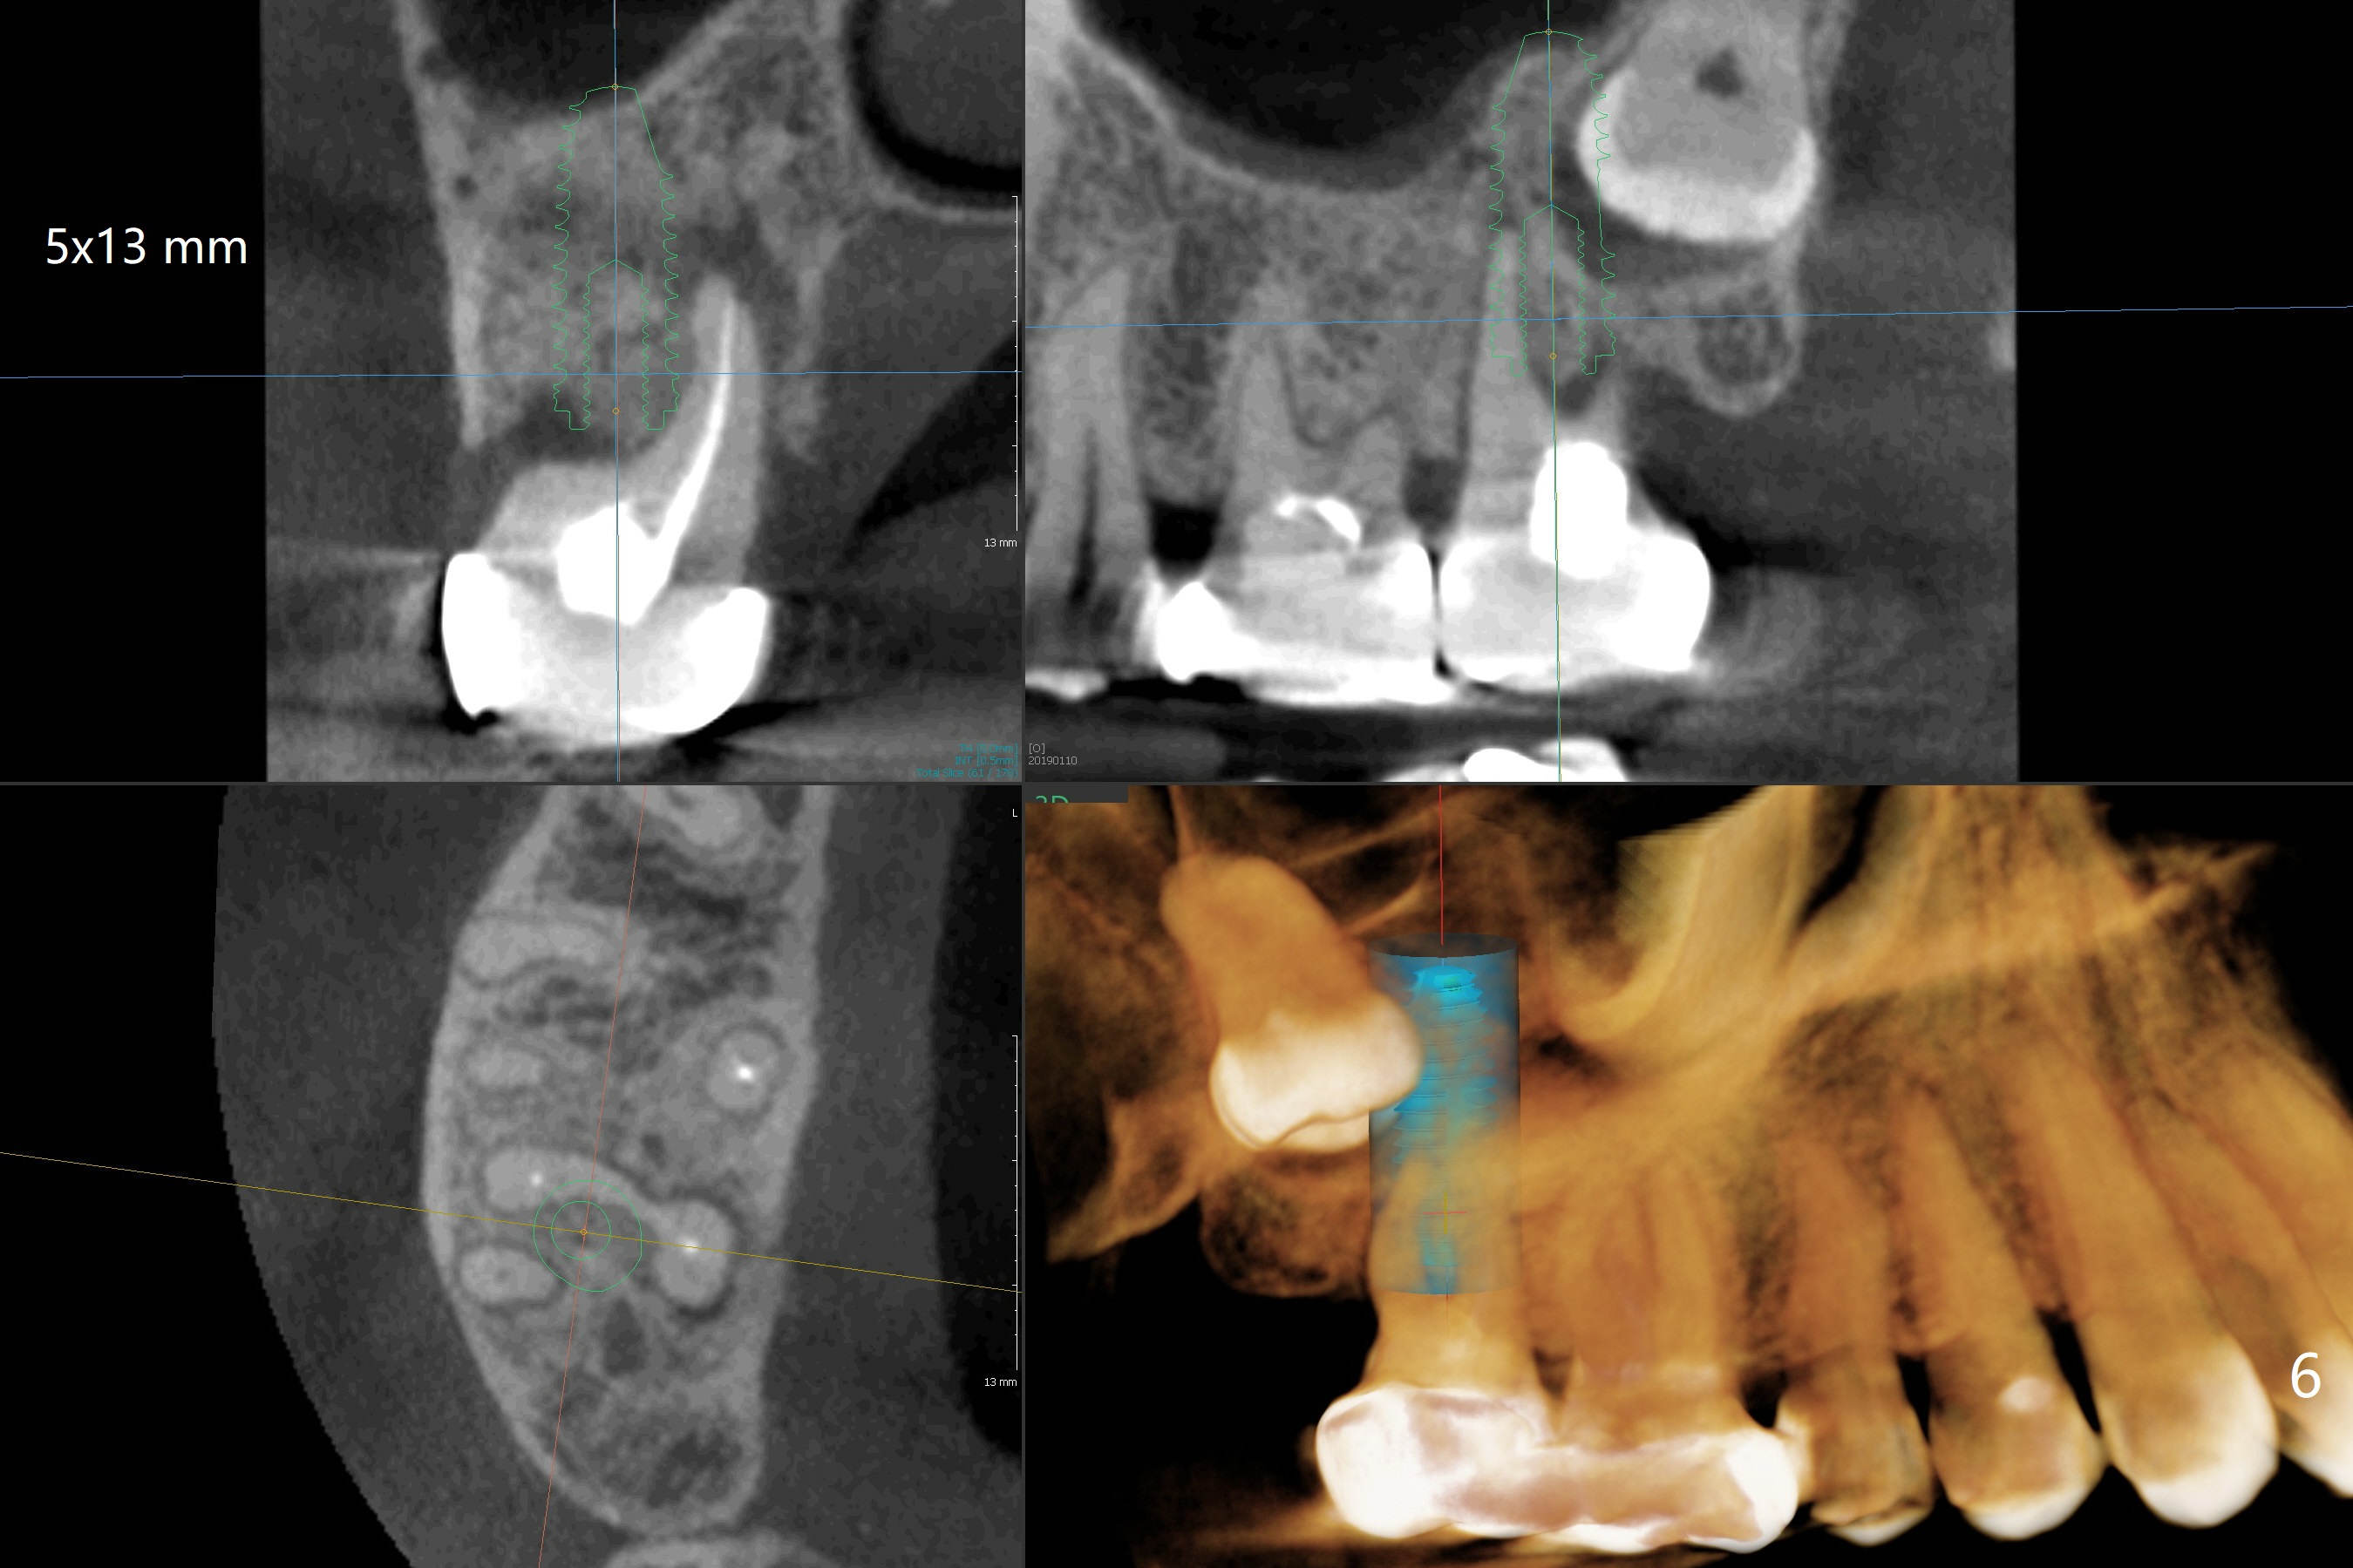

The tooth #1 should have been extracted buccodistally (Fig.3,4). Three or 4 months later, a 5x10 mm implant could be placed distopalatally superiorly to avoid removing the tooth #1 with ~ 1.5 mm clearance (Fig.5). To place an implant in orthopedic manner, the tooth #1 will be removed, while the implant should be longer (5x13 mm) to engage the bone superior to the socket of the tooth #1 (Fig.6).

The socket of #2 heals 13 days postop; it appears that the bone graft remains in place (Fig.7,8 *). The patient is instructed to return in 3-4 months for impression and CT for guide. The socket heals 4 months postop (Fig.9,10). She plans to have implant next year, since she wants to add another insurance. The patient returns for implant without removal of the third molar 2 years 4 months post socket preservation (Fig.11). A 5x7.3 mm implant can be placed without invading the sac of the impacted third molar (Fig.12). In fact the lab has a better plan. A lump of bone forms in the previous socket 1 year 4 months postop (Fig.13 *). The ridge is wide and dense (Fig.14). A narrow implant placed oblique could be longer (Fig.15), as compared to a wide, short one (Fig.12).